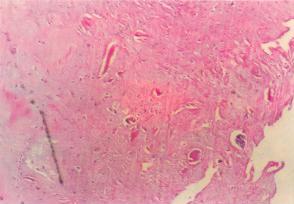

非特異性慢性炎,病變主要表現為纖維母細胞、血管內皮細胞和組織細胞增生,伴有淋巴細胞、漿細胞和巨噬細胞等慢性炎細胞浸潤,同時局部的被覆上皮、腺上皮和實質細胞也可增生。慢性炎症還可伴有肉芽組織的形成,這類炎症常見於有較大的組織缺損,此時肉芽組織在慢性膿腫、瘺管和慢性黏膜潰瘍的吸收和分解上起著重要作用。

慢性炎症除一般性和特殊性表現形式外,有時還可形成炎性息肉和炎性假瘤。炎性息肉(inflammatorypolyp)是在致炎因子的長期刺激下,局部黏膜上皮和腺體及肉芽組織增生而形成的突出於黏膜表面的肉芽腫塊,常見於鼻黏膜和宮頸。炎性假瘤(inflammatorypseudotumor)是由組織的炎性增生形成的一個境界清楚的腫瘤樣團塊,常發生於眼眶和肺。